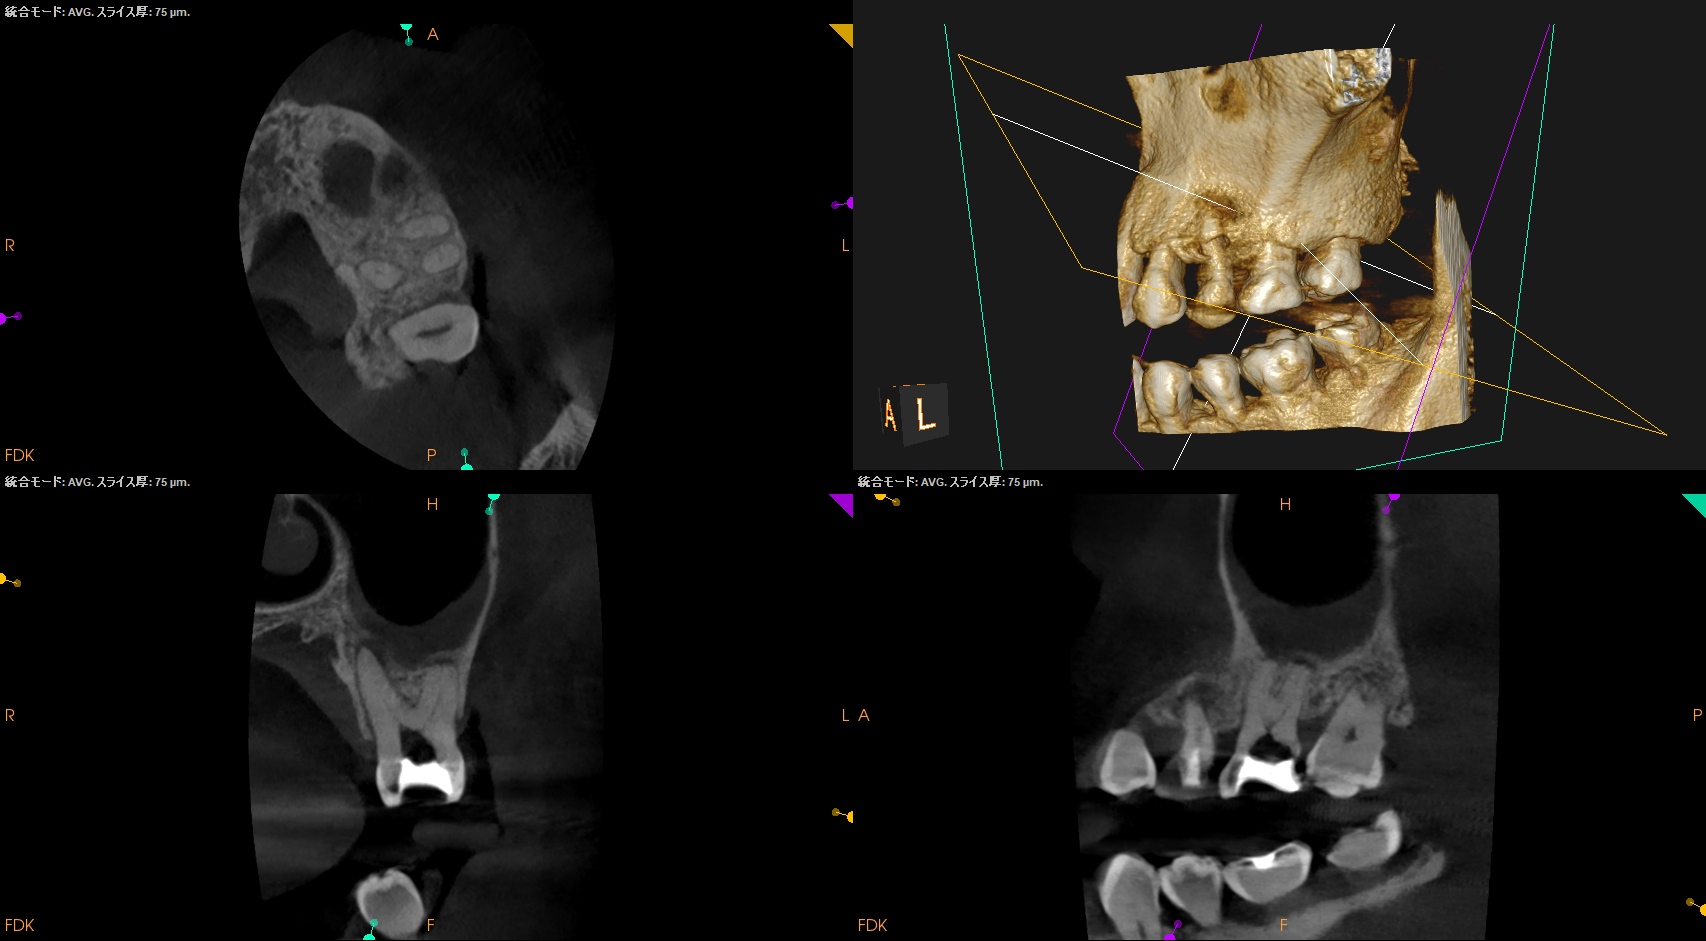

さておき、#13にも病変があるのがわかるので#13も分析した。

#13

#13は#14よりも大きな根尖病変がある。

ここも治療が必要だろう。

Pulp Dx: Previously initiated therapy

Periapical Dx: Symptomatic apical periodontitis

Recomended Tx: Re-RCT

では、再根管治療が必要な治療とわかるのだが、その成功率はどれくらいか?と言えば

穿通できれば86%

穿通できなければ60%

である。